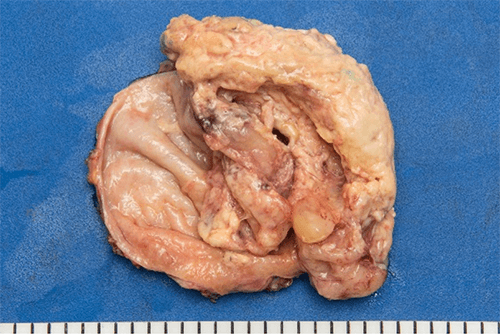

ET scan demonstrated avid uptake in the gallbladder and portal lymph nodes, which prompted an endoscopic ultrasound (EUS) and fine needle biopsy (Figure 2).

Figure 2: PET scan demonstrating a hypermetabolic mass in the gallbladder fundus and activity in the porta hepatis.